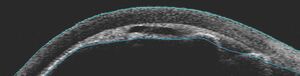

Patients often present with a red painful eye and decrease in vision. There is a higher incidence of malignant glaucoma in hyperopic eyes (short axial length). The intraocular pressure (IOP) is often very elevated but may present with “normal” or lower pressures leading to confusion about the diagnosis. Key to diagnosis is a flat chamber with both iris and lens positioned anteriorly and an almost flat anterior chamber (figure 1). The cornea shows signs of edema from both the elevated IOP as well as iris and lens touch. This should be distinguished from any post-operative swelling of the cornea. The opposite eye central anterior chamber is typically deep and this is one clue to distinguish malignant glaucoma from acute primary angle closure where the anterior chambers of both eyes are more symmetric. Ultrasound biomicroscopy can be useful in identifying anatomical structures when the corneal edema hinders slit lamp examination (figure 2). Optically clear “aqueous zones” have been described in the vitreous cavity although I have not seen this in my experience. History of intraocular surgery and laser should be explored including pars plana vitrectomy, trabeculectomy and the lasers mentioned earlier. Starting or stopping both cycloplegics as well as miotics have also been connected to the development of malignant glaucoma and should be part of the clinical history taking when possible.